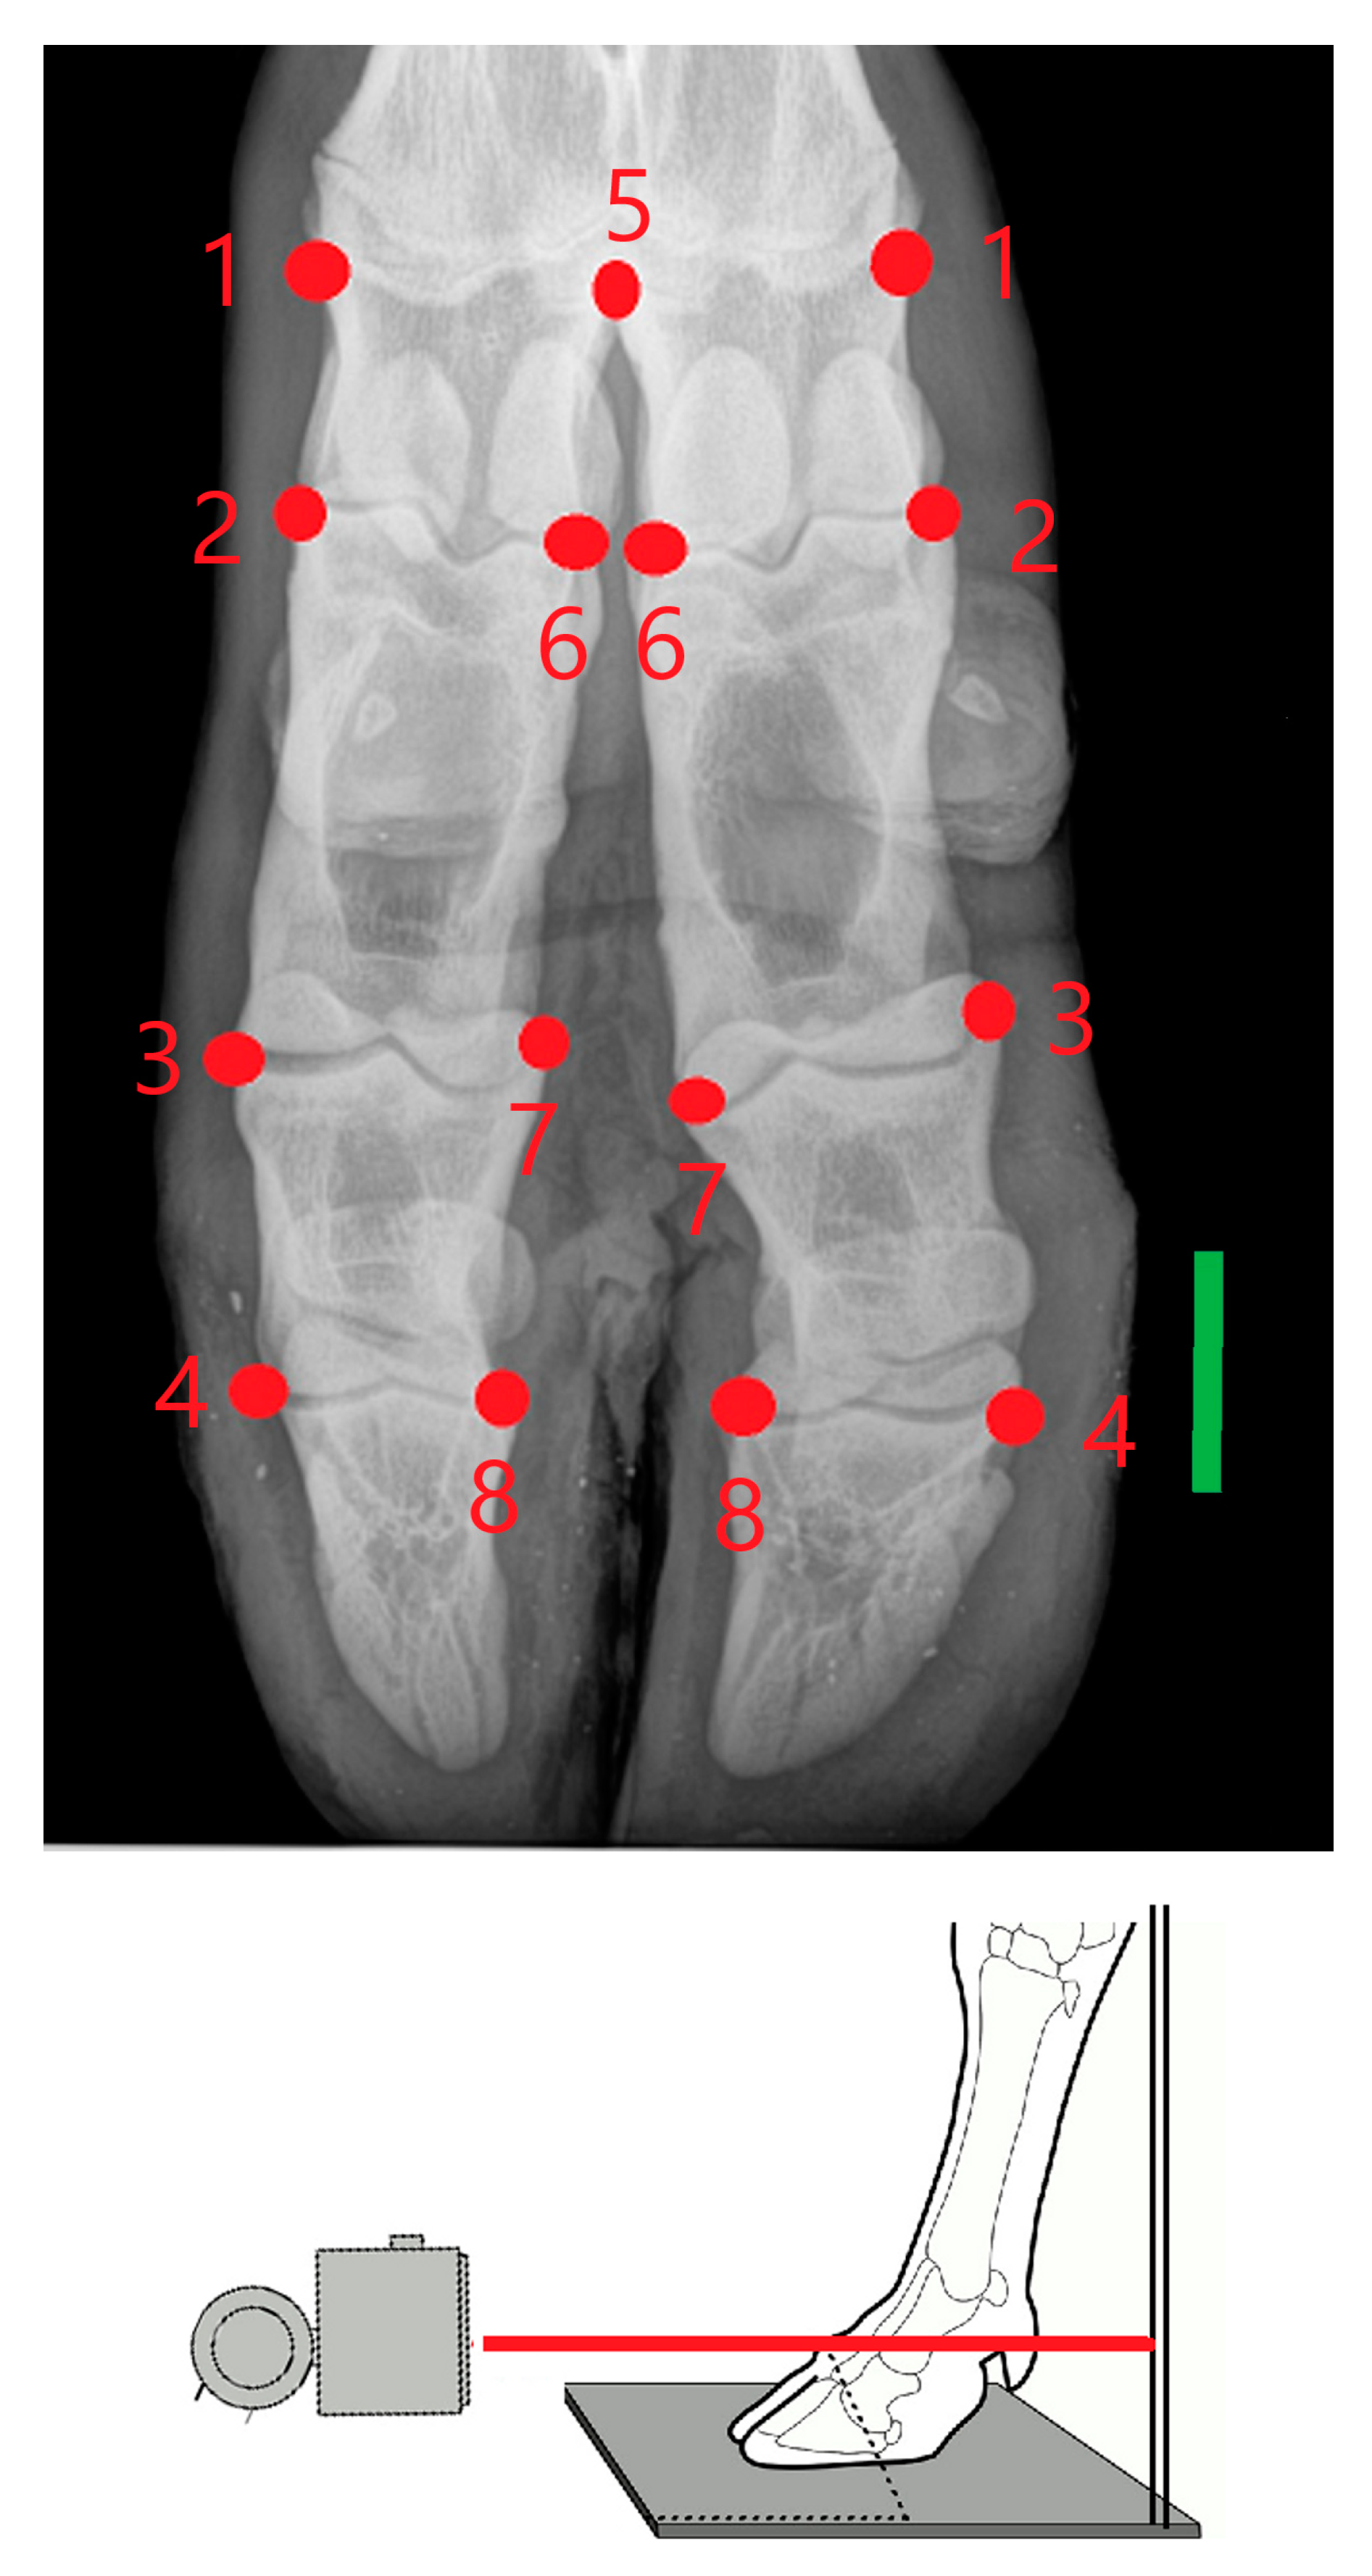

2. Materials and Methods

- Hoey, S.E.; Biedrzycki, A.H.; Livesey, M.J.; Drees, R. Radiographic anatomy of juvenile bovine limbs. Vet. Rec. 2016, 179, 546. [Google Scholar] [CrossRef]

- Rohlf, F.J. The tps series of software. Hystrix 2015, 26, 9–12. [Google Scholar] [CrossRef]

- Rohlf, F.J. Digitalized landmarks and outlines. In Stony Brook: Department of Ecology and Evolution; State University of New York: New York, NY, USA, 2010. [Google Scholar]

- Bookstein, F.L. Morphometric Tools for Landmark Data: Geometry and Biology; Cambridge University Press: Cambridge, UK, 1991. [Google Scholar]